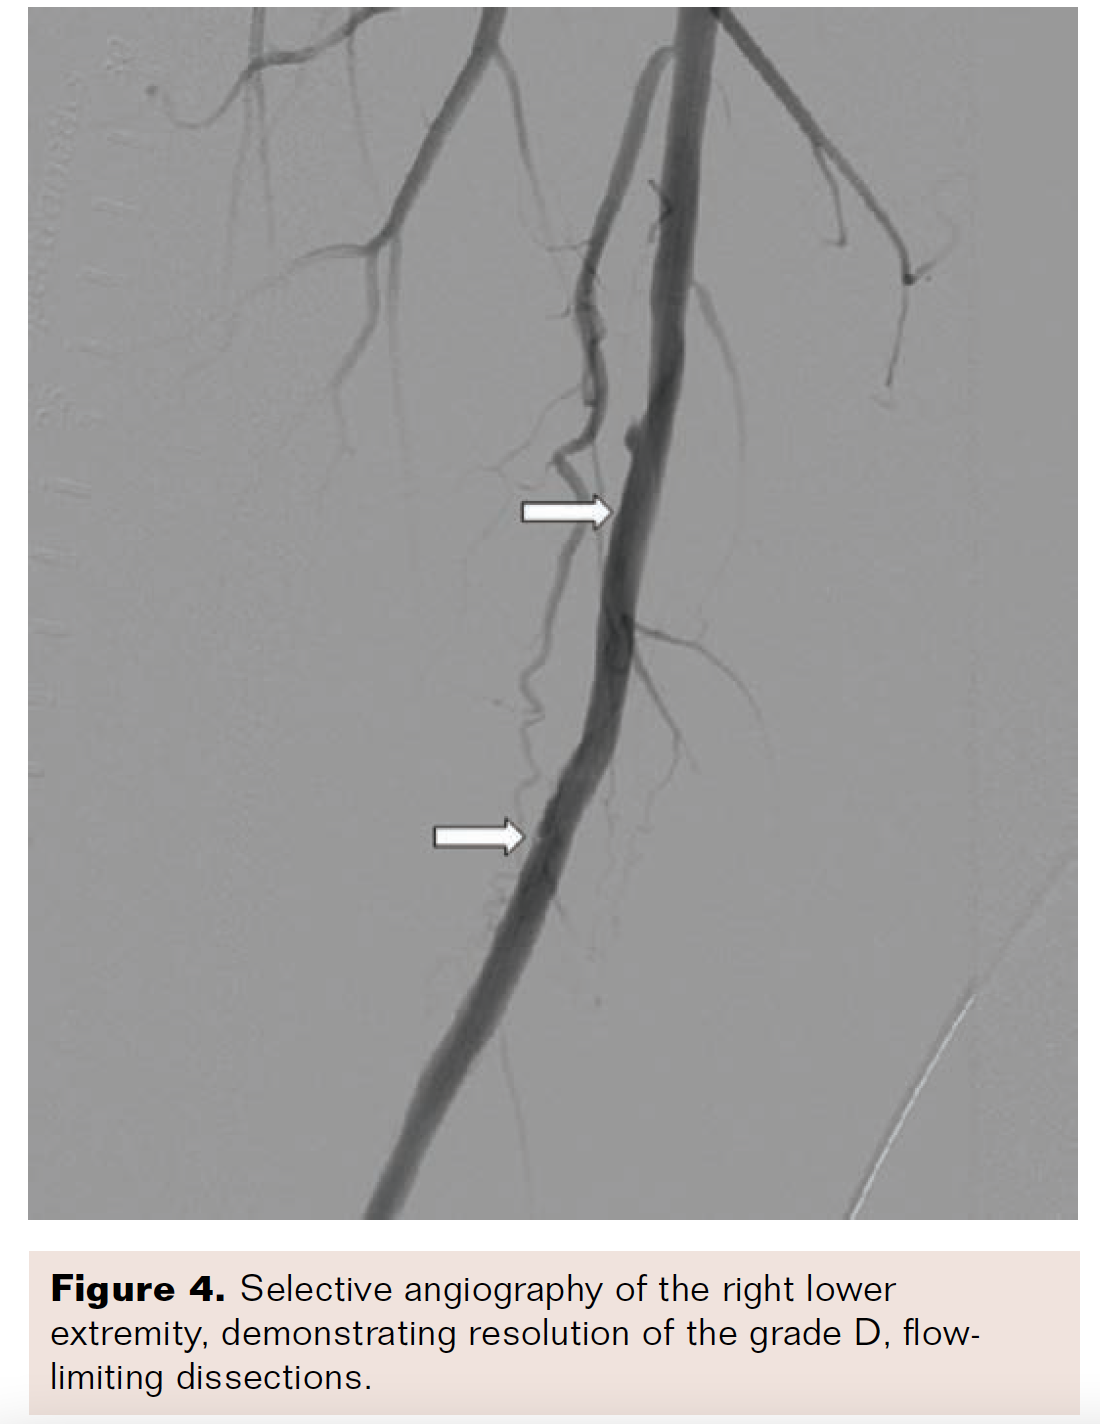

A .035-inch Rosen guidewire (Cook Medical) was exchanged through a Glidecath support catheter to accommodate the Tack implant .035-inch platform. The 6-French delivery catheter with the six preloaded, self-expanding Tack implants was loaded over the wire and positioned at the distal edge of the most distal dissection. Three Tack implants were deployed, with approximately 5 mm of distance between the stent edges. The remaining three Tack implants were deployed to resolve the proximal dissection (Figure 3). An additional balloon angioplasty with a 6 × 100 mm Armada PTA balloon was performed to seat the Tack implants in the desired location to optimize vessel flap apposition to the intima. Final angiography demonstrated resolution of the flow-limiting dissections, and post-intervention imaging confirmed less than 10% residual stenosis of the mid-right SFA (Figure 4).